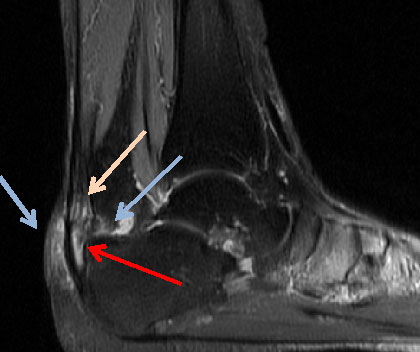

Abbildung 4: Das MRT des Rückfusses zeigt die unterschiedlichen Veränderungen, die mit einer Insertionstendinopathie einhergehen. Die präachilläre und retrocalcaneare Bursitiden (Pfeile) kommen zur Darstellung, sowie die intratendinösen Veränderungen.

Abbildung 4

Das MRT stellt den Goldstandard bei der Beurteilung von Sehnen und Weichteilgeweben dar. Die optimalen Sequenzen hängen häufig von dem verwendeten Gerät ab, zumeist werden jedoch T1-gewichtete und flüssigkeitssensitive STIR sowie Fett supprimierte intermediär gewichtete Sequenzen in axialer und sagittaler Schnittführung durchgeführt 12.  Das MRT ermöglicht insbesondere den Nachweis von intratendinösen Veränderungen und ansatznahen Partialrupturen. Daneben können im MRT das Paratenon, die ansatznahen Bursen und auch die differerentialdiagnostisch in Frage kommenden Strukturen wie die FHL-Sehne und das Os trigonum mitbeurteilt werden. Ein Ödem in der Tuberositas des Calcaneus kann degenerative Veränderungen der Gleitfläche zur  Achillessehne hin anzeigen. Aufgrund der Schnittführung und des zum Teil geringen Kontrastes ist die Identifikation und Lokalisation von Ossifikationen jedoch gelegentlich zur operativen Planung nicht ausreichend (Abb 4).